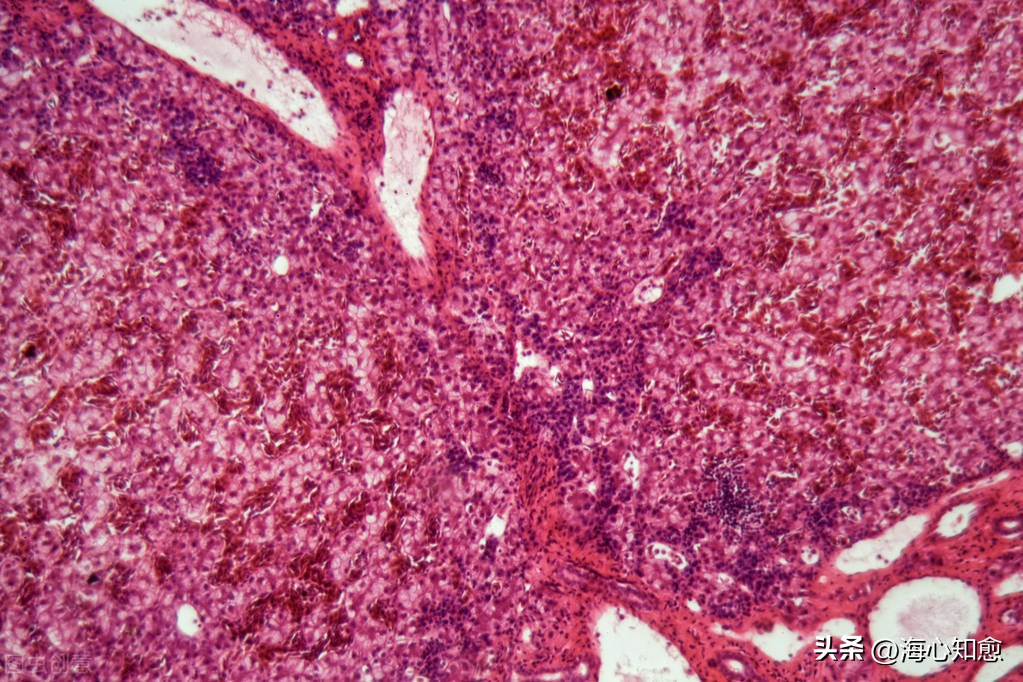

丙氨酸转氨酶异常,常反映肝实质细胞损害,或反映肿瘤细胞的大量坏死。

肿瘤患友丙氨酸转氨酶明显增高,手术死亡率也明显增高。